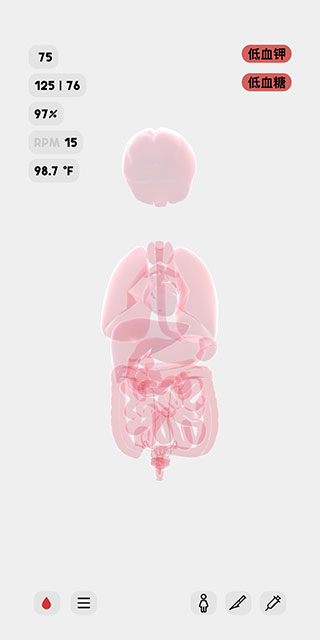

2、这时候我们可以看到人体模型已经成功创建,显示的是人体各个器官的透视图,左上角显示是人体的各个主要信息参数指标。

8、屏幕右上角显示的是该人体模型的异常状态,例如现在,她正处于低血钾和低血糖的状态中。

当然,生命人体模拟器这款游戏还为玩家提供了手动的状态设置,因此你可以为人体模型设置成不同的状态,然后观察其反应,或者监视他的生理变化。游戏中为每个器官都提供了专业的参数指标,如果你是医学生,就可以很好地掌握这些指标信息,以至于快速做出判断和处理措施。如果你是一位休闲玩家,那也没关系,通过这款游戏,你不仅会学到很多专业的医学知识,而且还能体验一下当医生的感觉。总之这款游戏适应任何玩家群体,感兴趣的小伙伴不妨下载尝试一下!